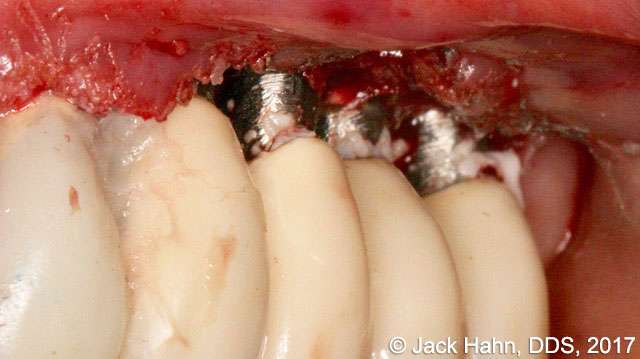

CASE #6 Laser Crown Lengthening

Dr. Hahn performed crown lengthening on old Sterioss implants that he placed over 25 years ago. The photos show the surgical site before the crown lengthening, immediately following the crown lengthening, and 30 days postoperatively. Dr. Hahn notes the excellent healing in the post-op visit.